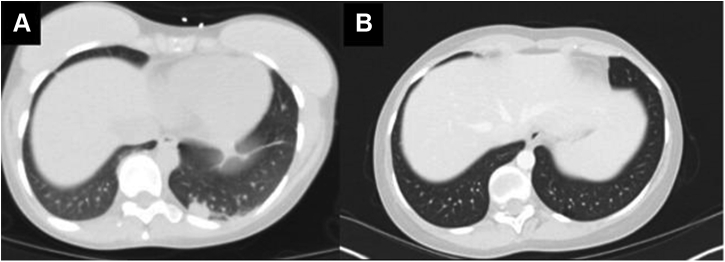

A 27-year-old woman presented after a tonic-clonic seizure. Result of brain magnetic resonance imaging revealed multiple ring-enhancing lesions, and results of computed tomography of the chest and abdomen noted a 2 cm by 1.1 cm left lower lobe lung mass and mediastinal lymphadenopathy (Figs. 1A–C and 2A and B). Result of computed tomography-guided biopsy of a mediastinal lymph node with fluorescence in situ hybridization testing confirmed ALK-rearranged adenocarcinoma, with programmed death-ligand 1 at 35%, and no additional actionable mutations on OnkoSight next-generation sequencing assessment. She underwent stereotactic radiosurgery to the brain metastases, and alectinib 300 mg twice daily was initiated.

Figure 2.

(A) CT chest with contrast at the time of diagnosis. (B) CT chest with contrast 4.5 years after diagnosis. CT, computed tomography.